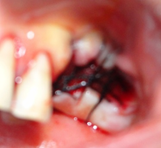

Todos dentes condenados tiveram que ser extraídos. As remoções foram feitas com muita cautela para não haver rompimento da crista óssea, assim como do septo interdental. Esse procedimento deve ser realizado em todas exodontias, para preservar o máximo de tecido ósseo alveolar.

Os dentes depois de extraídos, os alvéolos limpos e curetados rigorosamente. Importantíssimo, netas cirurgias, é realizar os procedimentos como uma cirurgia de retalho periodontal, pois as paredes das bolsas periodontais devem ser totalmente removidas, com uma lâmina número 15, realizando uma incisão de bizel interno, para a remoção total do tecido interno que forma a bolsa, eliminando assim as bactérias infiltradas neste tecido. A exposição de uma mucosa gengival sadia, após o deslocamento do retalho total, é importantíssima, para a cicatrização. A camada basal do epitélio gengival, exposta, tem um enorme potencial de regeneração, o que será importante nas técnicas de Regeneração Óssea Guiada.